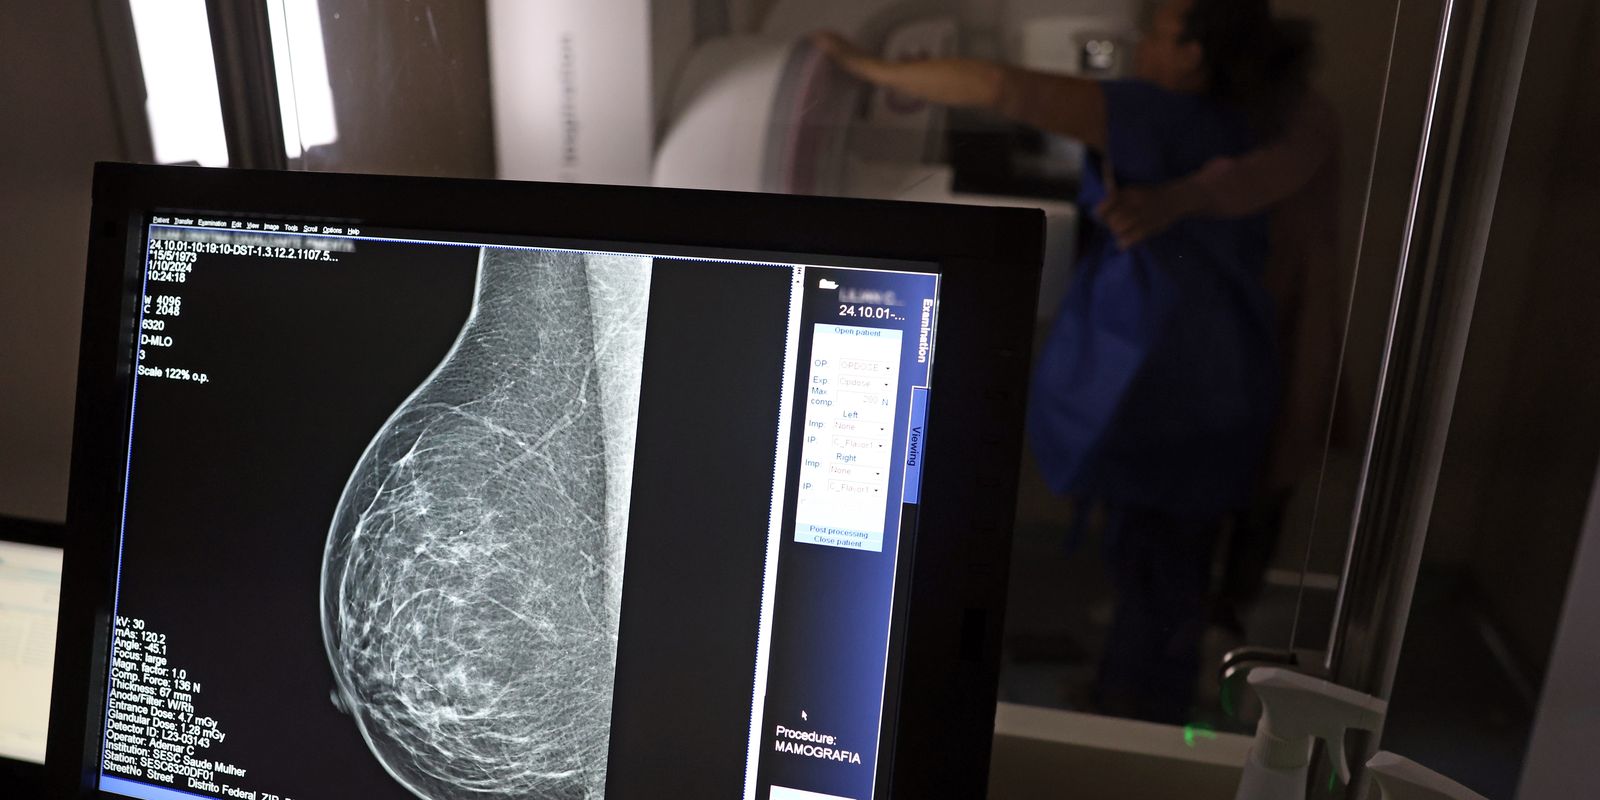

Falta de acesso a mamógrafos limita prevenção do câncer de mama

No mês de conscientização sobre o câncer de mama, um relatório destaca a importância de acesso igualitário ao rastreamento e tratamento da doença. Segundo o Atlas da Radiologia no Brasil, do Colégio Brasileiro de Radiologia e Diagnóstico por Imagem (CBR), o acesso aos mamógrafos ainda é um desafio.

O país tem 6.826 equipamentos registrados, sendo 96% em funcionamento. Metade deles está disponível no Sistema Único de Saúde (SUS), responsável por atender 75% da população. Isso equivale a 2,13 mamógrafos por 100 mil habitantes dependentes do SUS.

Na saúde suplementar, que cobre 25% da população, o cenário é mais favorável: 6,54 aparelhos por 100 mil beneficiárias, quase o triplo da rede pública. O Acre exemplifica essa disparidade — são 35,38 mamógrafos por 100 mil habitantes na rede privada, contra 0,84 no SUS.

O Brasil tem uma cobertura muito baixa de mamografias: 24%. O ideal recomendado pela Organização Mundial da Saúde é de 70%. Mesmo em lugares como o estado de São Paulo, que tem a maior concentração de mamógrafos do país, a taxa gira em torno de 26%.

Em setembro, o Ministério da Saúde ampliou as diretrizes de rastreamento, recomendando que mulheres entre 40 e 49 anos realizem mamografias, mesmo sem sintomas. De acordo com o Instituto Nacional do Câncer (Imca), mais de 73 mil mulheres recebem o diagnóstico de câncer de mama anualmente no Brasil.

“O que é efetivo na redução da mortalidade é você descobrir o tumor antes de ter sintoma clínico. Quanto menor o tumor, melhor para a gente descobrir o tratamento e maior a chance de cura. E a gente só consegue fazer isso com exames de imagem", diz Ivie.

Ela explica que no caso de diagnóstico de um câncer de mama com menos de 1 cm, a chance de cura é de 95% em cinco anos, independentemente se ele é do tipo mais agressivo. "E esses tumores só vão ser detectados na mamografia. Essas pessoas que têm que ir fazer mamografia são mulheres saudáveis. Não são mulheres doentes”, acrescenta.